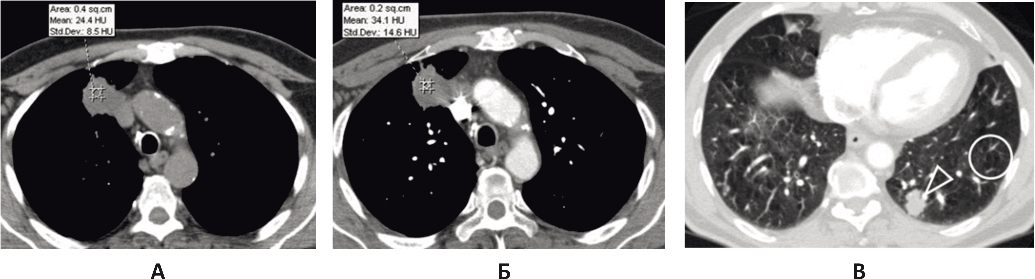

10.12.2017 г. отмечены умеренное нарастание дыхательной недостаточности, появление одышки в покое, снижение SpO2 крови до 86%. На рентгенограмме грудной клетки от 10.12.2017 г. (рис. 2) зафиксирован малый апикальный пневмоторакс справа, толщина воздушной прослойки составляла 17 мм. Выполнено дренирование правой плевральной полости, отошел воздух, состояние пациента улучшилось, одышка в покое не беспокоила, SpO2 крови увеличилась до 94%. По плевральному дренажу наблюдался слабый, но постоянный сброс воздуха. Проводилась активная аспирация воздуха из плевральной полости на среднем разрежении.

Рис. 2. Рентгенограмма грудной клетки от 10.02.2017 г. Малый апикальный пневмоторакс справа

11.12.2017 г. у пациента одномоментно развилась массивная подкожная эмфизема грудной клетки, наросла дыхательная недостаточность, увеличился сброс воздуха по дренажу правой плевральной полости. Больной в экстренном порядке переведен в отделение реанимации. На КТ грудной клетки – тотальный пневмоторакс слева с полным коллабированием легкого, справа легкое практически расправлено (рис. 3). Выполнено экстренное дренирование левой плевральной полости. Продолжена активная аспирация воздуха из обеих плевральных полостей. В результате состояние пациента улучшилось, подкожная эмфизема уменьшилась, дыхательная недостаточность регрессировала. По дренажам обеих плевральных полостей наблюдался сброс воздуха: крупнокалиберный – справа, мелкокалиберный – слева. Наличие двусторонних бронхоплевральных свищей не позволило предпринять видеоторакоскопическое вмешательство, требующее раздельной интубации главных бронхов, поэтому была продолжена интенсивная терапия в условиях реанимации, санационная бронхоскопия.

Рис. 3. КТ грудной клетки от 11.12.2017 г., состояние после дренирования левой плевральной полости. А: в левой плевральной полости, в мягких тканях грудной клетки, в средостении визуализируется свободный воздух (черные стрелки); Б: компрессионные изменения нижней доли слева, небольшое количество жидкости в плевральных полостях (белая стрелка)